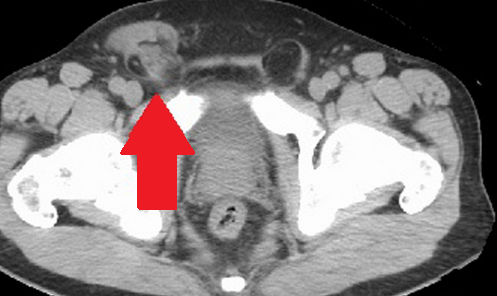

Evident dilation of the left ureter -- yellow outline. Green outline -- Chordoma (Courtesy Dr. V. Penopoulos)